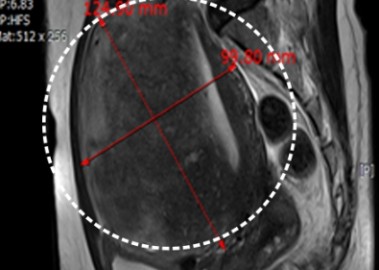

거대 자궁선근증 치료 사례